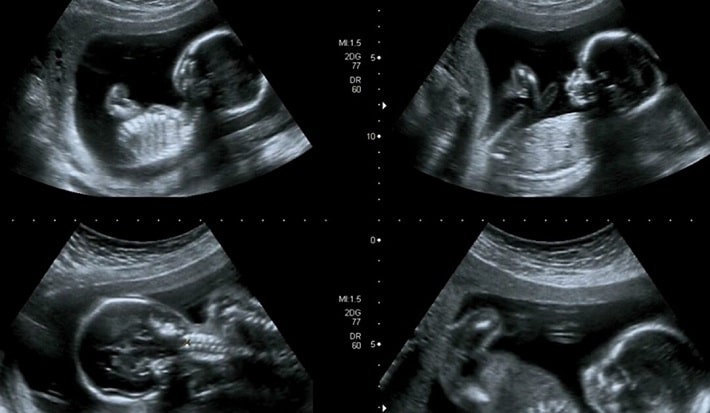

سونوگرافی آنومالی اسکن

سونوگرافی

1404/11/19

دوران بارداری پر از لحظات شیرین و البته پر از پرسش های بی پایان است. یکی از مهم ترین ایستگاه های این مسیر، سونوگرافی آنو...